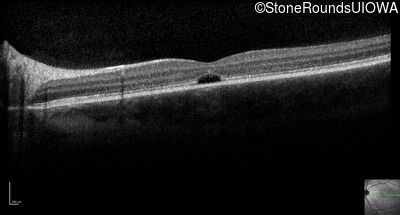

Optical Coherence Tomography - Left - 20/80 -1

Exemplar / OCT Stack

OCT Stack